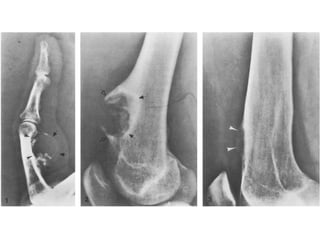

OSTEOID OSTEOMA

• This is a small, benign tumour formed of osteoid and woven bone

• These lesions are most common in young patients but are rare

• They are more common in men than women.

proximal femur.

most often seen in the posterior arches.

• Osteoid osteomas most often present with pain, which classically is

• When in close proximity to a joint, they can result in stiffness and

• In the spine, they can cause muscle spasm and scoliosis.

• Plain X-ray demonstrates an area of dense sclerosis with a

small, rounded area of osteolysis which is often obscured by

• Isotope bone scan is positive and the central nidus of the

• Histology demonstrates a packed mesh of thin, woven bone

• The mature osteoid corresponds to the nidus, which is

soft tissue also showing features of inflammation.

time will regress and usually burns out over a variable period

• The preferred method of treatment is by CT-guided

successful in eradicating the lesion with a dramatic resolution